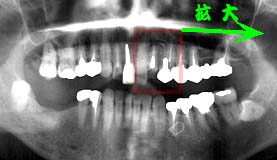

42歳 男性 │7抜歯により「7挺出

主訴は、│7の動揺が気になる

口腔清掃状態は、比較的良好であったが、歯石の沈着が多く歯槽骨の吸収も中程度で年齢の 割には著明であった。主訴である│7は根管治療の不備による根尖病巣と歯周疾患進行に 伴う歯槽骨の吸収により周囲骨すべてが破壊されていた。

処置および経過:

│7は保存不可能であるので抜歯を行い、ムシ歯の治療と歯周初期治療を 行ったのちメインテナンスに移行。 1ヵ月毎のメインテナンスを継続したことにより歯周疾患の進行はほぼ停止し、 歯周組織は安定した状態を保ち、経過良好の中4年を経過。 歯周疾患進行状況を把握するためにパノラマ撮影を行った結果比較的満足のいく 情報が得られたものの、│7抜歯に伴う「7挺出の速さに少々戸惑うと 同時に、「7周囲骨の挺出に驚嘆。

考察:

歯牙挺出に伴う周囲骨の挺出は、日常臨床では決して稀な出来事ではない。 しかし、挺出前の状況と挺出後の状況を並べて比較できる機会は比較的稀なことである。 歯周疾患の進行が停止した状況下では、歯槽骨付着位置に変化がないままに、歯根の 挺出と伴に歯槽骨も挺出する事実を思い知らされた症例である。

この事実は歯槽骨再生を願う多くの方々に大きなヒントになるものと確信する。